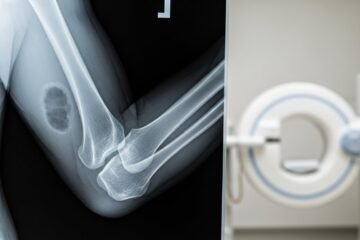

Radiographie du Coude au Maroc : Guide Complet pour Patients

Vous ressentez une douleur intense au coude après une chute ? Vous vous demandez où faire une radiographie du coude au Maroc, combien cela coûte et comment obtenir un remboursement ? Ce guide répond à toutes vos questions sur cet examen d’imagerie médicale essentiel. Que vous ayez subi un traumatisme ou souffriez de douleurs chroniques, […]